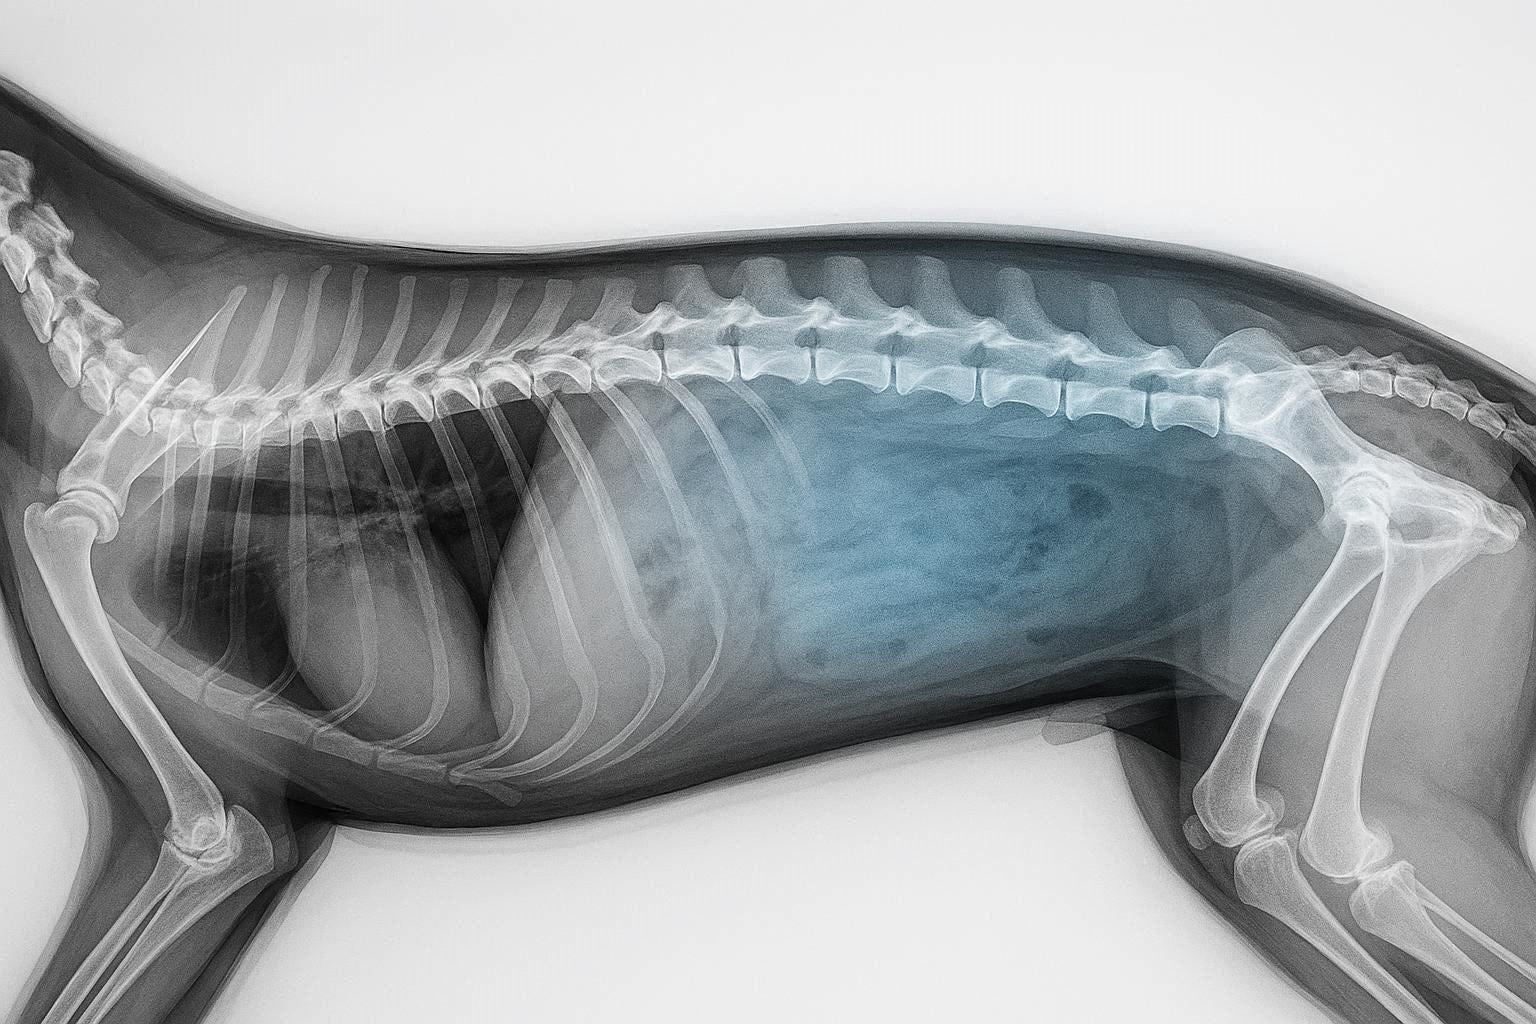

X-ray of a dachshund with IVDD

Enfermedad del disco intervertebral (EDIV) en perros salchicha: cómo detectarla a tiempo, tratarla y proteger la columna vertebral de su perro